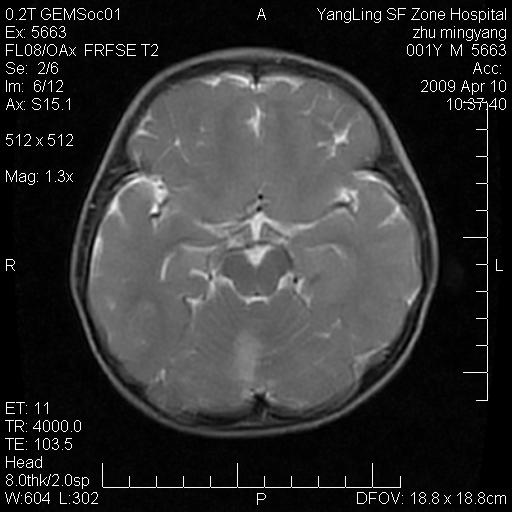

患者:1岁半,两天前外伤收住我院,ct检查小脑占位

考虑星形细胞瘤,建议增强

髓母细胞瘤或血管母细胞瘤,增强后可以鉴别;影像资料见 <。鱼博浪老师的《中枢神经系统ct与mr鉴别诊断》 小脑部肿瘤章节。

髓母细胞瘤或血管母细胞瘤!支持!

支持考虑髓母细胞瘤

考虑----髓母细胞瘤可能性大

考虑髓母细胞瘤或室管膜瘤。

支持髓母细胞瘤。

考虑髓母细胞瘤。

考虑髓母细胞瘤或星形细胞瘤

考虑髓母细胞瘤.

考虑髓母细胞瘤可能性大。

小脑肿瘤.考虑髓母细胞瘤可能.

就病灶部位及临床资料首先考虑髓母.